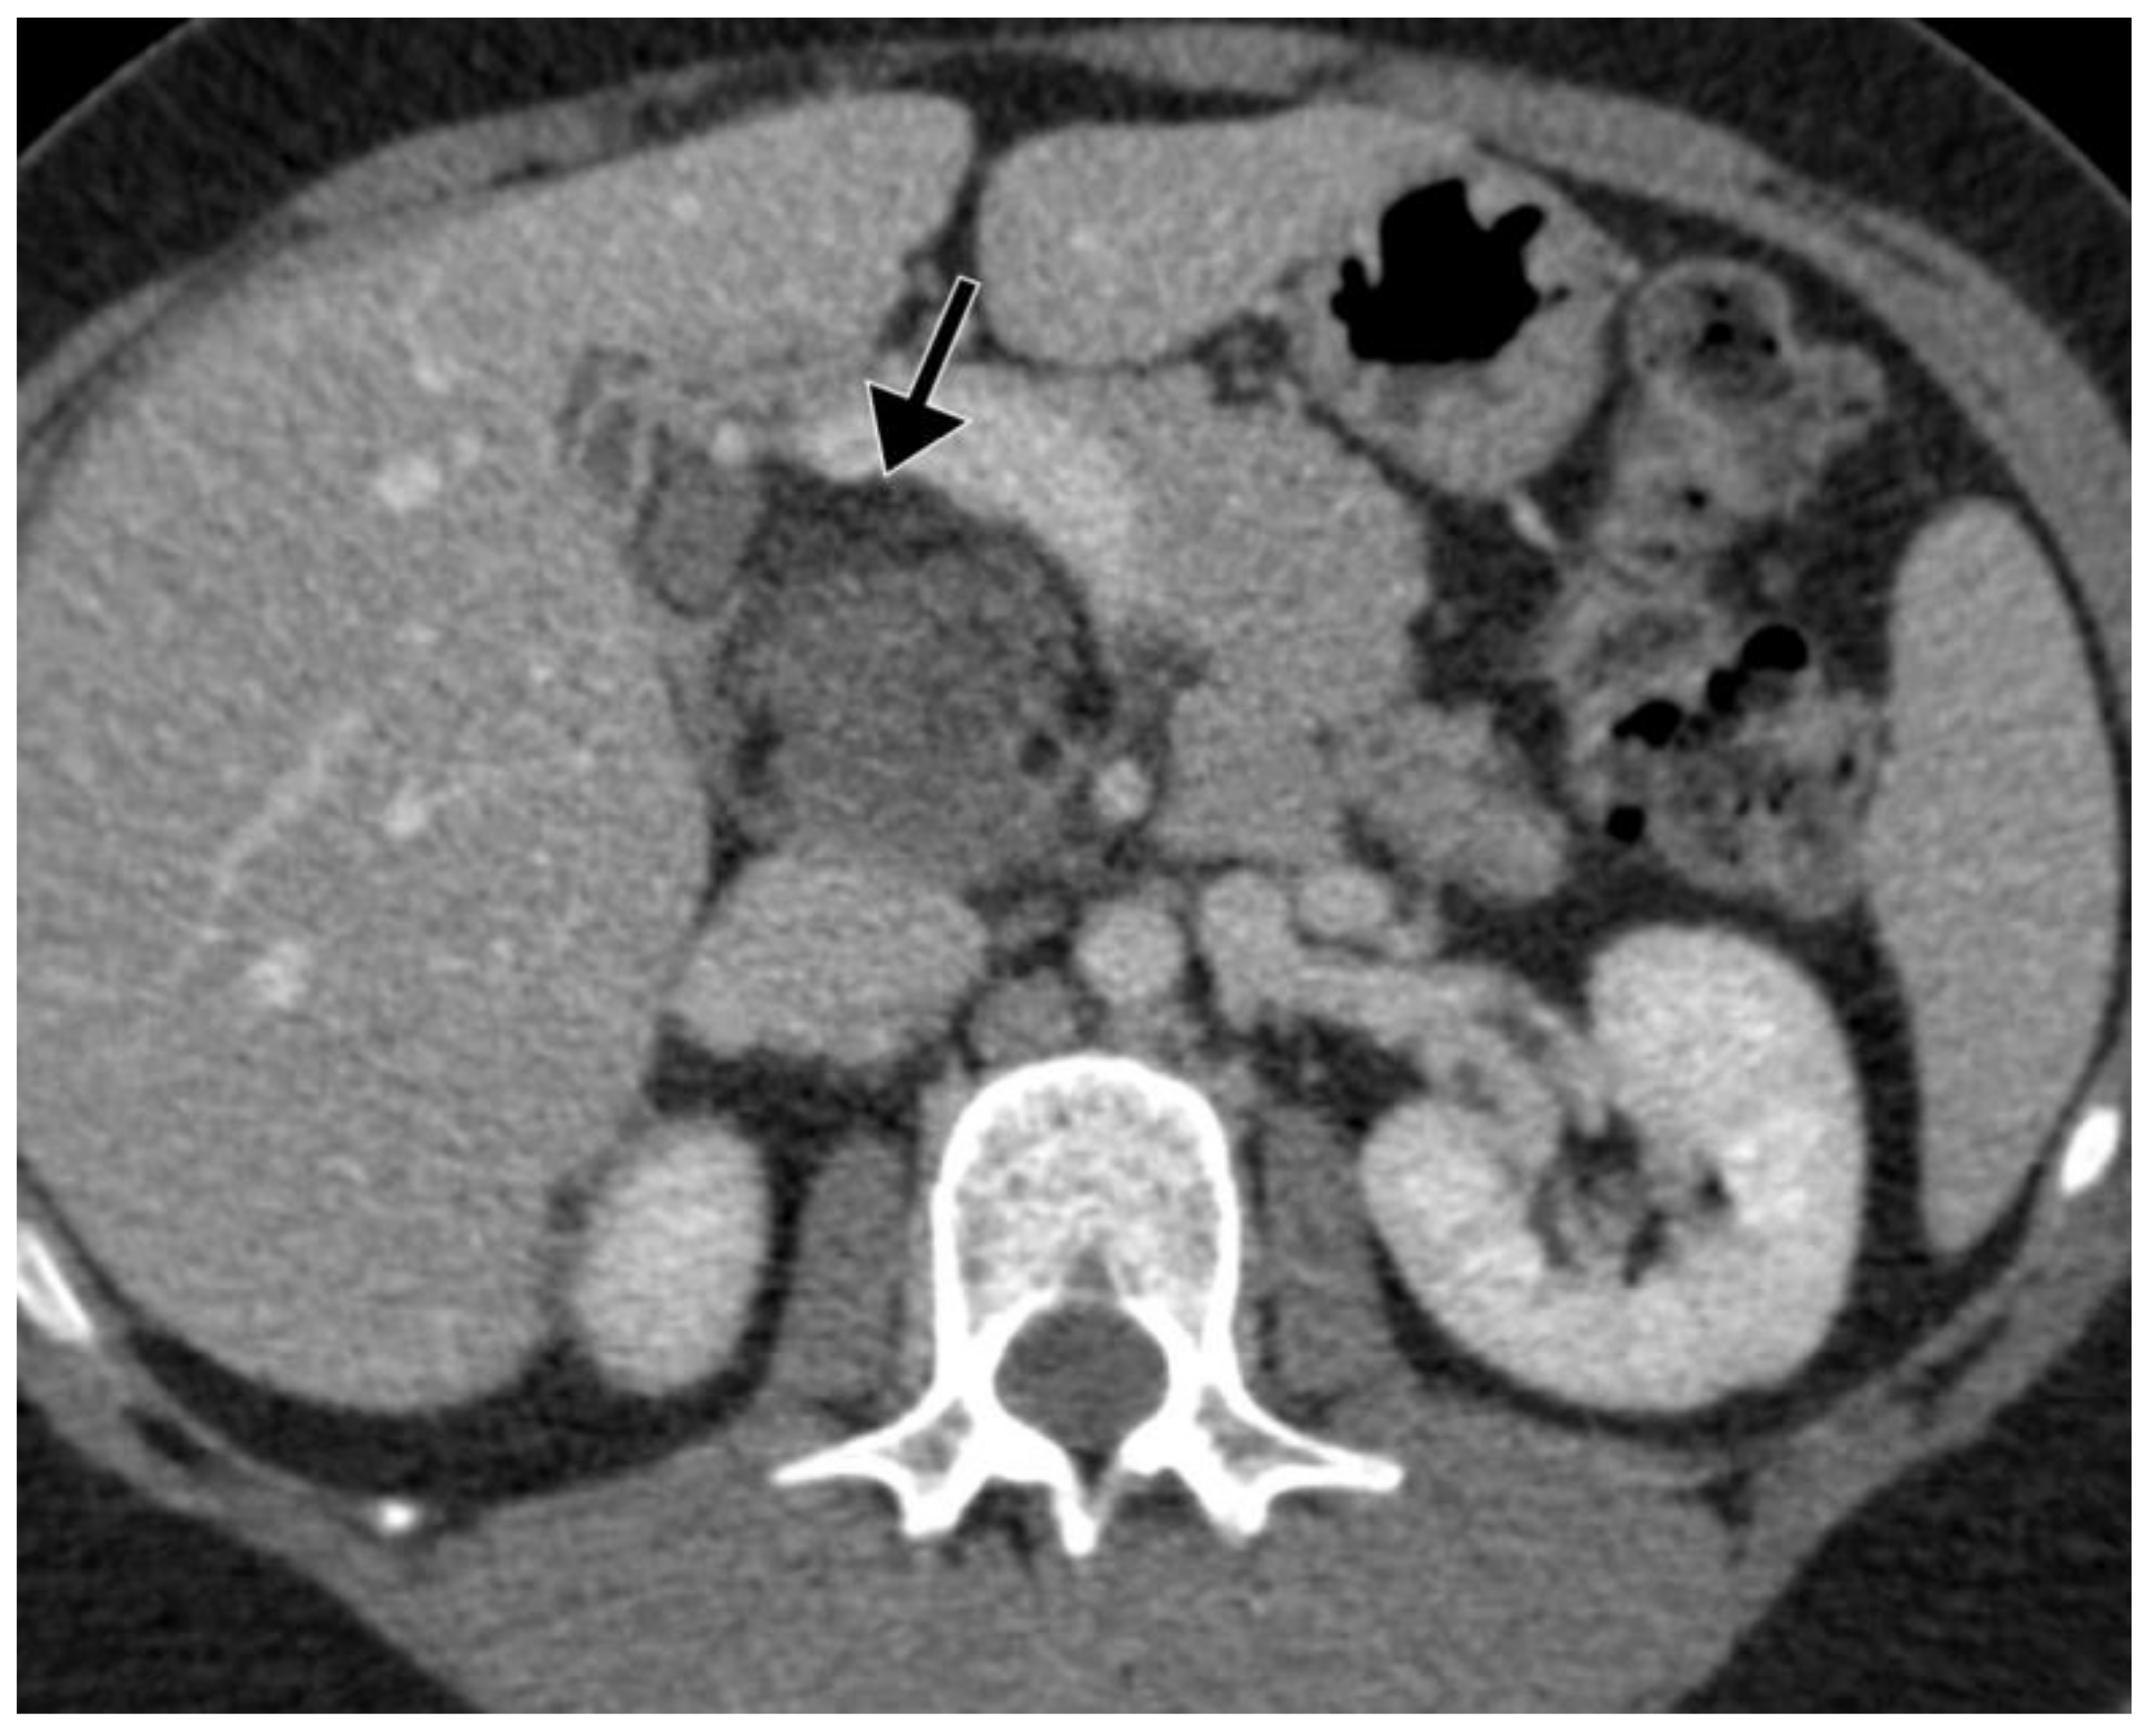

| Djokic et al., 2022 (current paper) | 33 | F | UA pain | Head | PPPD | 85 × 56 mm | 6 mm | <2% |